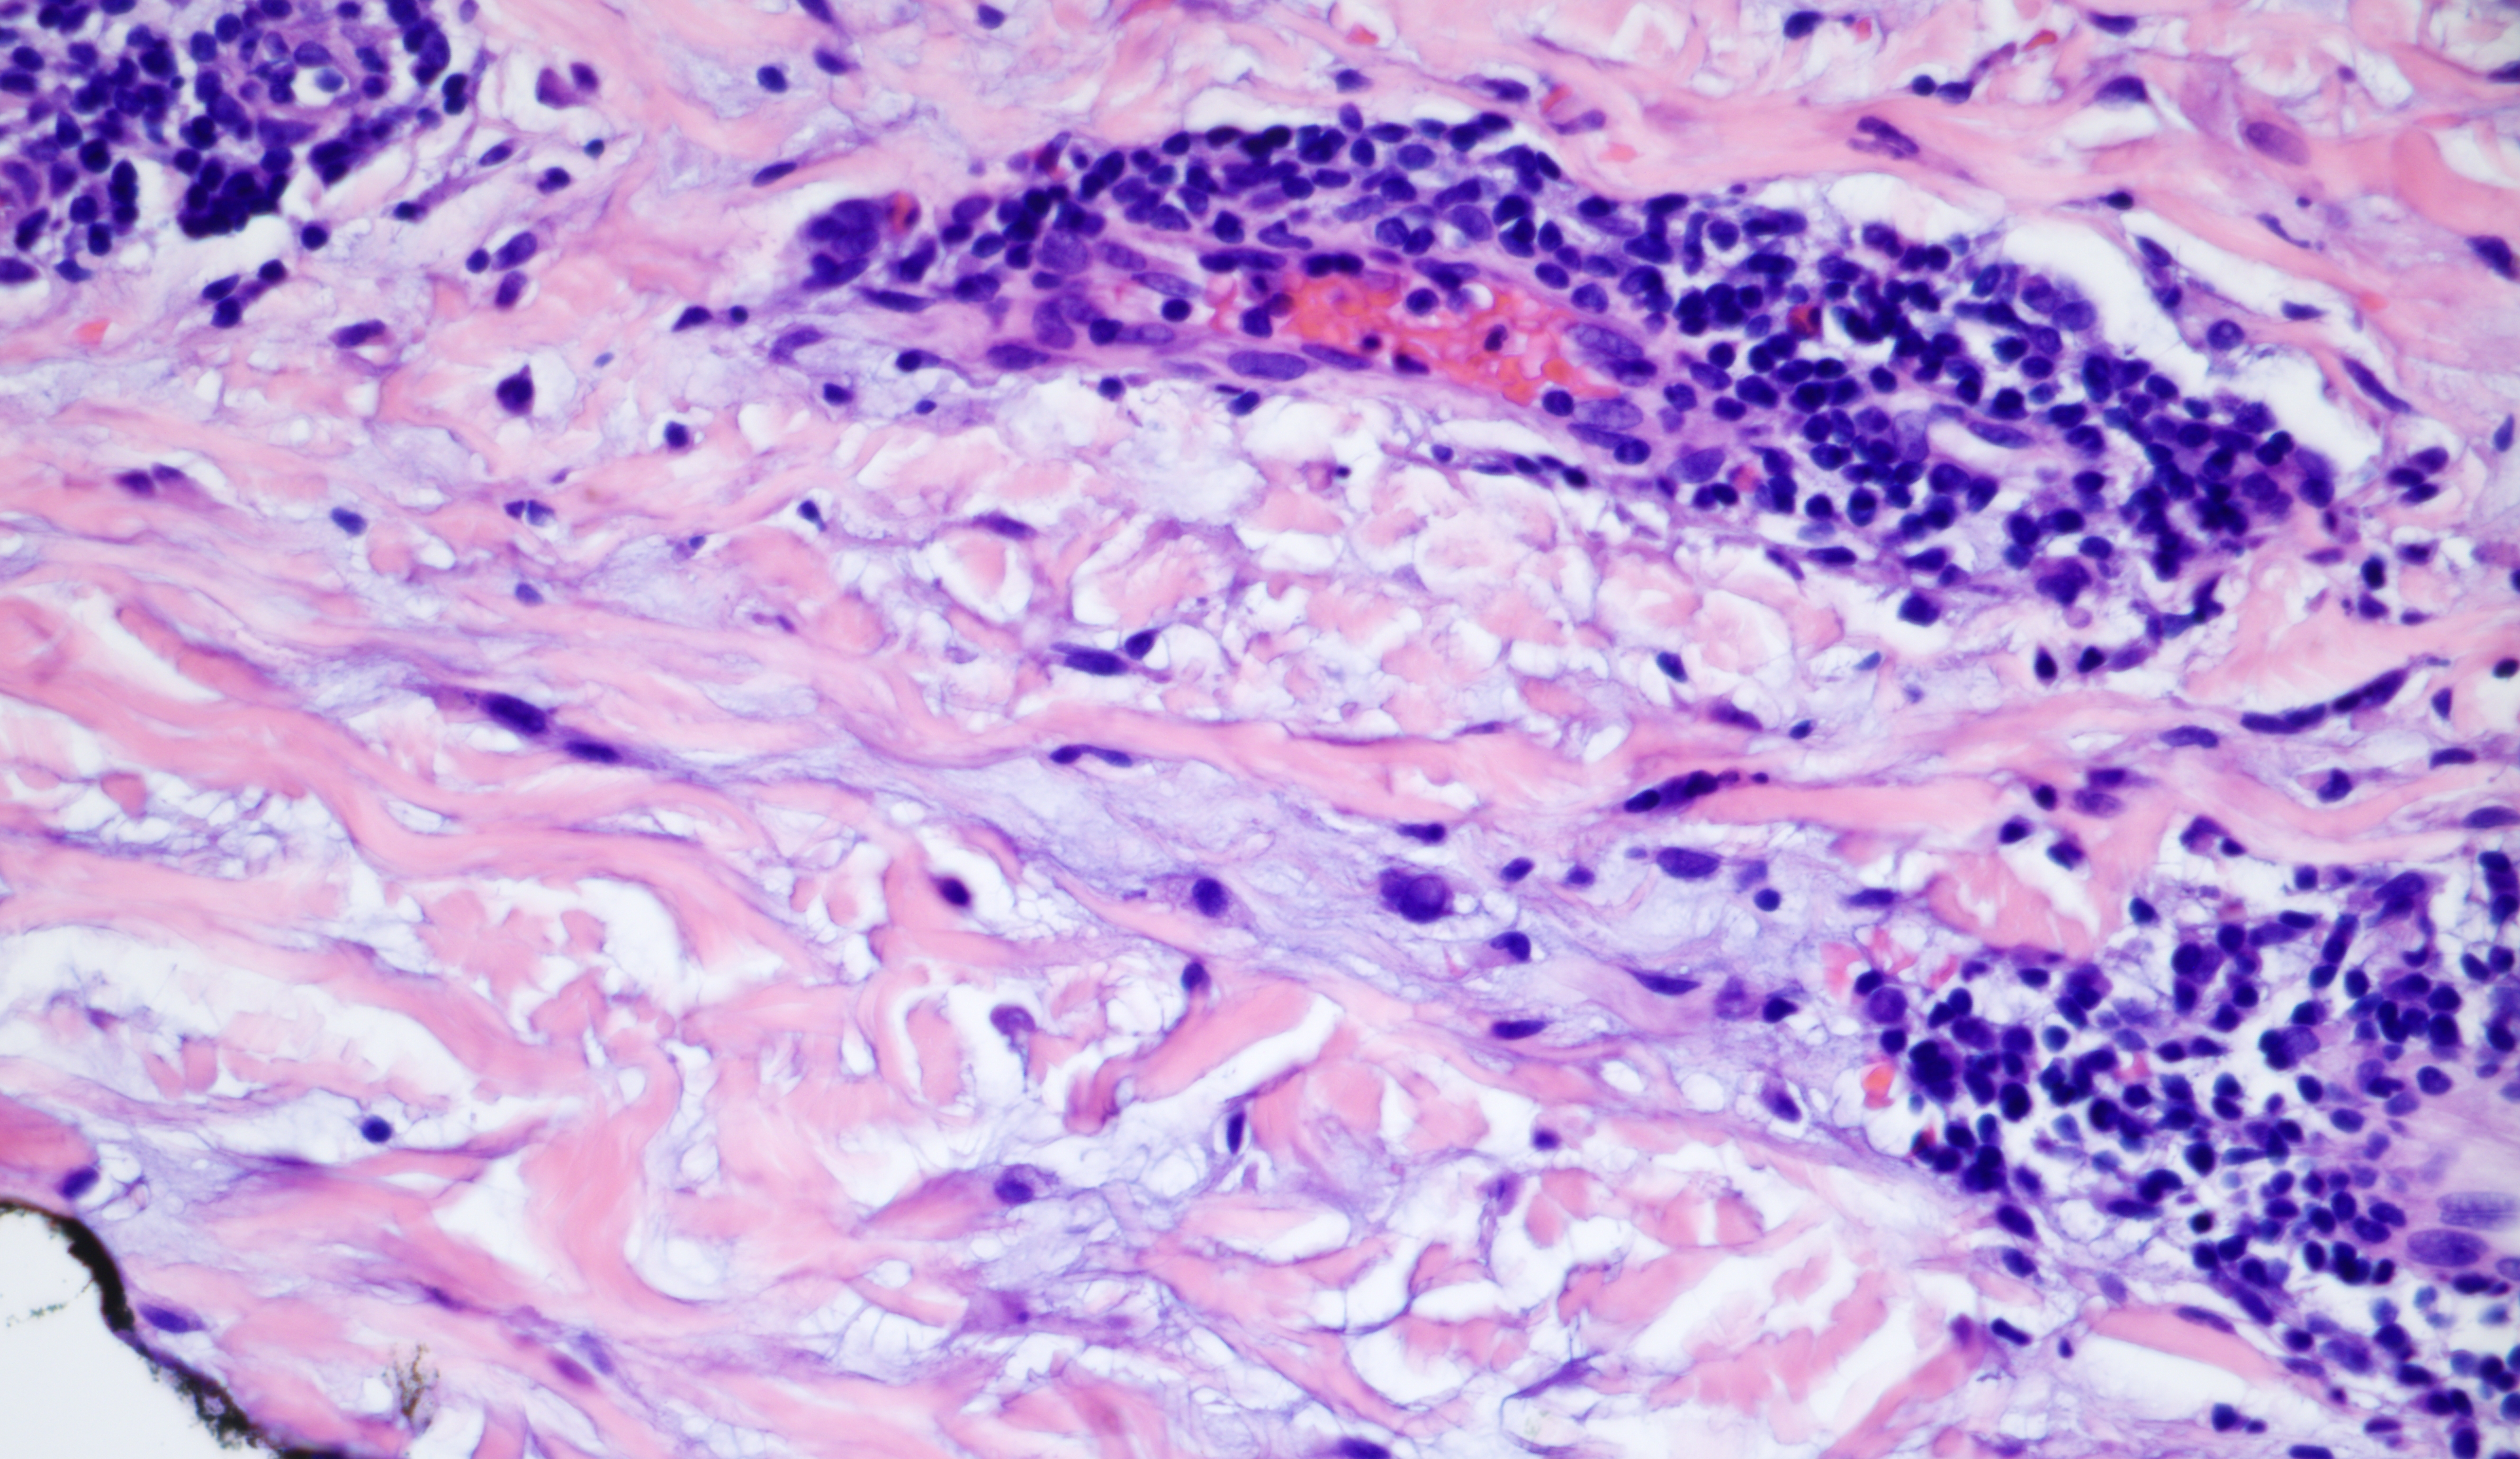

47-year-old Caucasian woman with erythematous macules, patches, and keratotic plaques on neck and upper chest